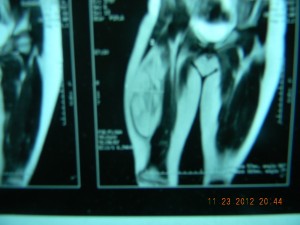

Juan Ángel, 9 años, sufría de un lipoma gigante que por 4 años fue incrementando de tamaño en su muslo derecho. Juan fue sometido a una operación en uno de los centros públicos de San Pedro Sula, pero resultó ser incompleta por lo que el tumor volvió a crecer.

Al tener un lipoma tan gigante, surgen problemas en la deambulación, dolor, y trastornos psicológicos en la autoestima del niño. Si no se hubiese extraído el lipoma hubiese seguido creciendo de tamaño hasta llegar al punto de no permitirle a Juan caminar, así como compresión del paquete vascular nervioso de la pierna con lesión muscular y desarrollo normal de la pierna afectada.